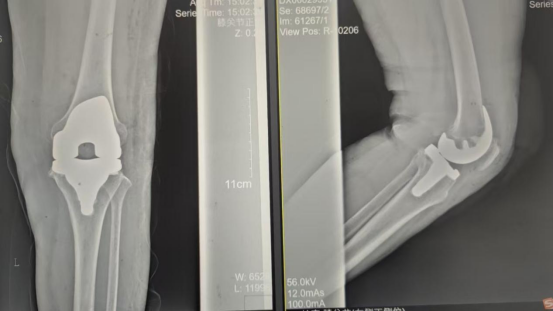

因张女士患有高血压病2级(高危)、心律失常(窦缓)且伴有肺部熏染等并发症。。。。。。穆志亮主任和叶龙安主治医师凭证张女士的病情制订详细手术方案 ,,,,,建议在全麻下行“左人工全膝枢纽置换术”。。。。。。

手术当天张女士怀着忐忑的心情进入手术室 ,,,,,然而陪同着麻醉医师的平和攀谈和手术护士的温馨付托 ,,,,,在不知不觉中逐步睡着 ,,,,,手术很是顺遂。。。。。。术后经医护职员的全心治疗与护理 ,,,,,张女士康复出院 ,,,,,最终解决了10余年的病痛。。。。。。

术后影像资料

365英国上市(集团)有限公司-Official website